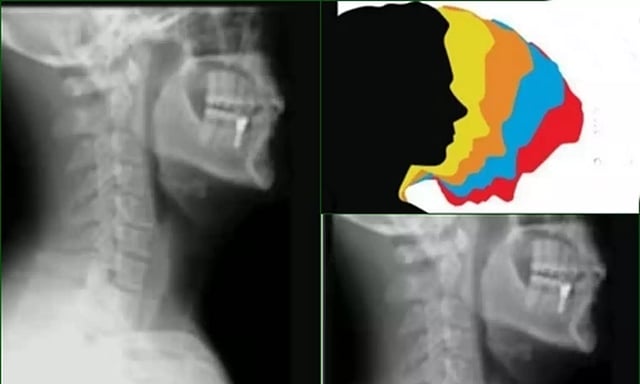

FARIDABAD: There has been a significant rise in "text-neck syndrome", especially among the young adults, which account for about 70 per cent in the outpatient department, said city doctors on Monday on the occasion of World Spine Day.

According to doctors at Amrita Hospital Faridabad, exposure to long hours in front of screens, coupled with poor posture and inadequate ergonomics in the workplace, is causing the young adults to be susceptible to spine-related conditions like "text-neck syndrome".

The syndrome can be defined as where the neck muscles become strained and stiff, causing long-term spinal complexities, the experts said.

"Poor posture has become the most common cause of back and neck pain among our OPD patients. Remarkably, nearly 70 per cent of our OPD patients fall into this category. Poor screen etiquette is also a leading contributor to such pain. People often use their gadgets with their neck bent for prolonged periods, leading to a condition called "text-neck syndrome. Individuals between the ages of 25 and 45 are the most commonly affected by postural back pain," said Dr Tarun Suri, Head of Spine Surgery at Amrita Hospital Faridabad.

Studies show that poor posture is the primary cause of neck and back pain in young and mid-age individuals, leading to work loss, hospital visits, and treatment expenses. Over time, it damages spinal discs, causes muscle spasms, and may lead to chronic pain, disc degeneration, and even surgery in severe cases.